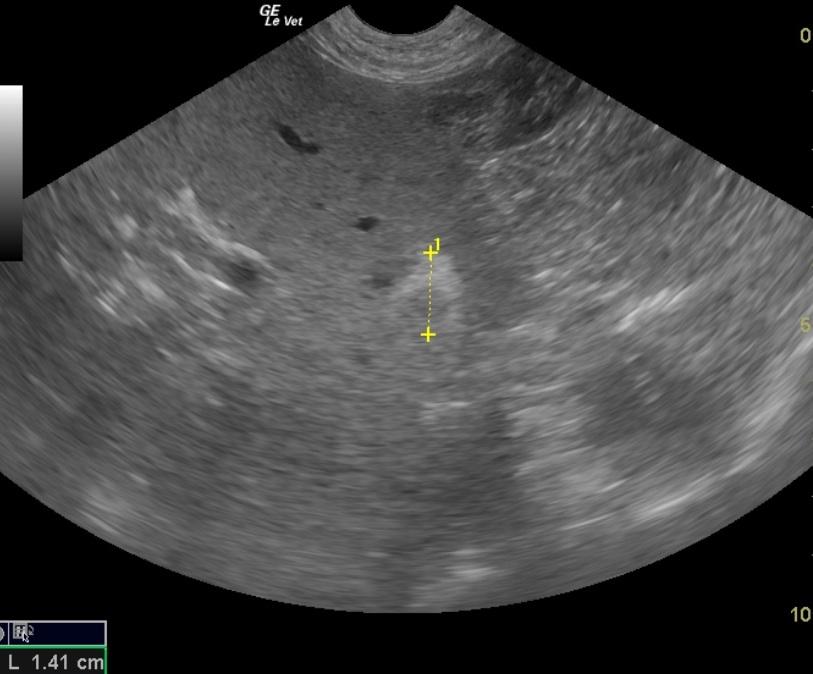

A 10 year old SF Labrador was presented with a history of not doing right and having an ACTH stimulation test at the low end of normal. Additional history was that she would vomit when taken off a chicken/rice diet. Current therapy was Pepcid. Abnormalities on urinalysis were inappropriate SG, proteinuria, pyuria, and the presence of cocci and triple phosphate crystals Abnormalities on serum biochemistry were hyperkalemia and elevated ALP activity. T4 was low. Survey radiographs were within normal limits. The patient was treated with Cerenia following another bout of vomiting.